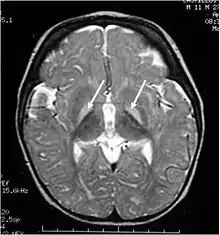

Unbound plasma bilirubin past a threshold exerts neurotoxic effects through triggering diversified metabolic cascades. It decreases oxygen consumption and increases neuronal apoptosis directly or indirectly through release of pro-inflammatory enzymes by glial cells.[32] Primary targets affected are the basal ganglia, brainstem and cerebellum due to differential tissue binding, bilirubin uptake and cell's higher sensitivity to injury.[32][33]